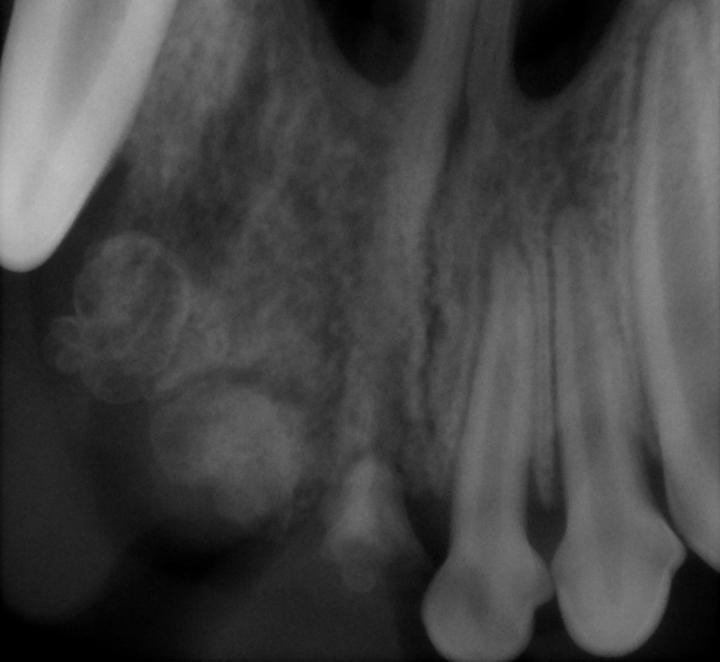

b Dental radiography is essential in any lesion where there are teeth absent. In this radiograph

radiodense structures are present in the areas of the absent incisor teeth. These possibly

represent deformed incisors of which the normal development was hampered secondary to acute trauma

to the developing tooth buds. As a result, dental hard tissue was formed haphazardly and therefore

no normal tooth structure is evident.